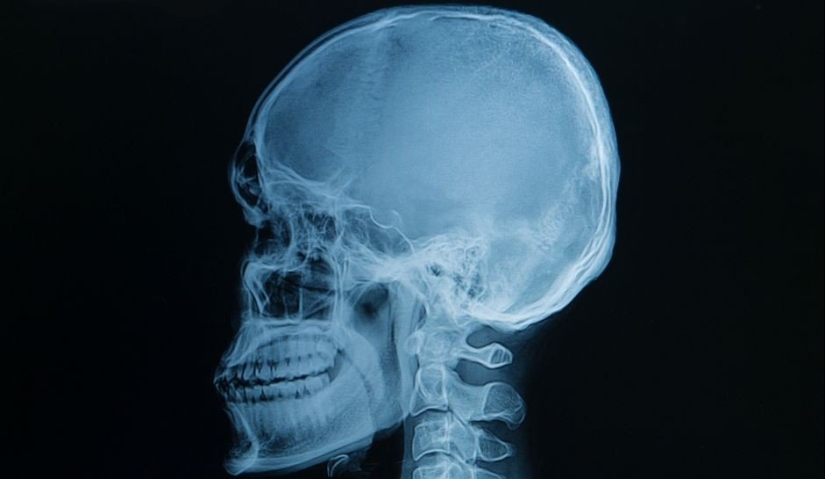

An image that made dozens of people shudder. This is what human teeth look like inside the jaw.